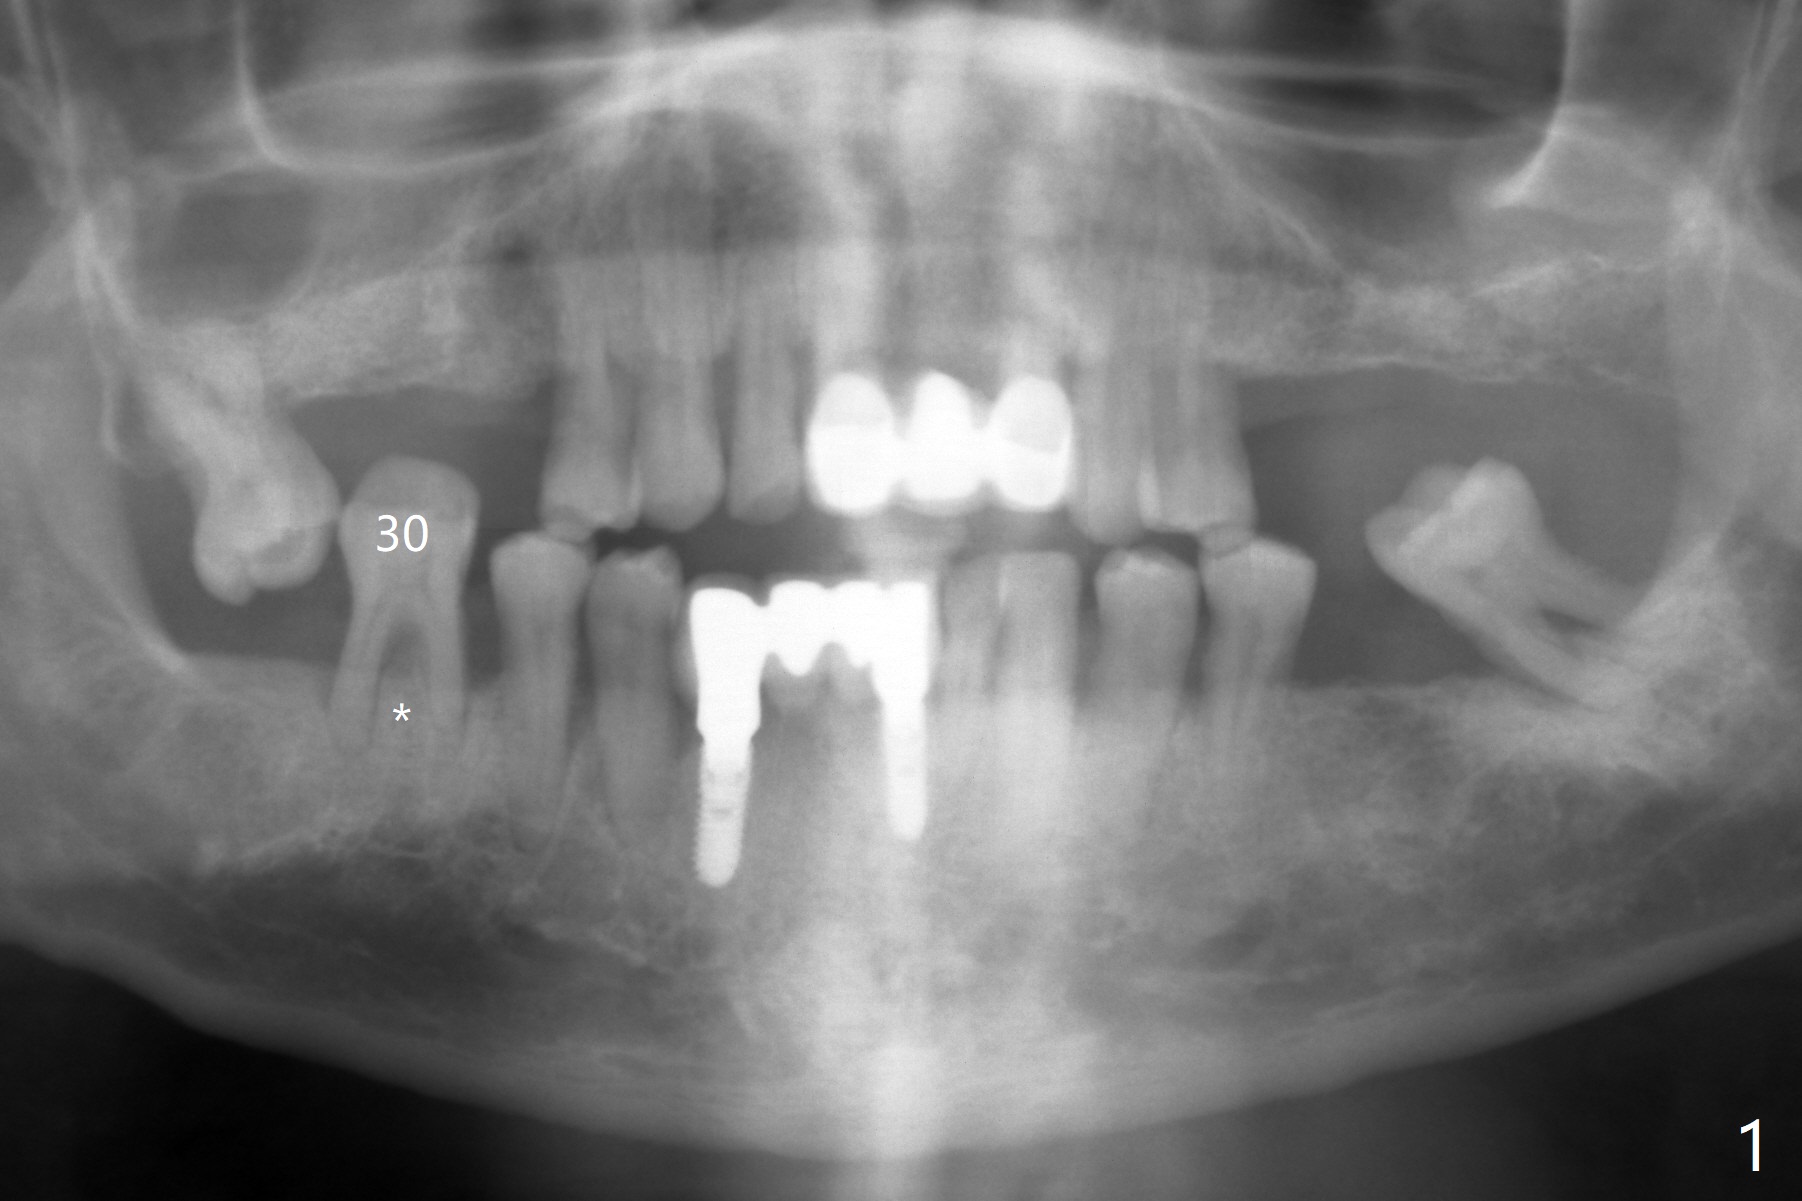

A 52-year-old man with poor dentition has concept of socket preservation when he wants extraction at #30. There is bone loss with the presence of the septum (Fig.1,2 *). Mixture of Vanilla graft and Osteogen is packed around the septum (Fig.3). With blood supply from the septum, the allograft should be more efficiently converted to the native bone than without the septum. The socket is closed with Osteogen plug and suture (Fig.4). In fact the bone height increases by 2.4 mm over the septum 11 months postop (Fig.5,6). In contrast there is apparently no bone regeneration in the socket of #28 four months postop without bone graft (Fig.7). Implant to be placed in the "empty" socket may fail. With bone graft, the ridge at #30 is higher than the surrounding bone 18 months postop (Fig.8 ^) with formation of the cortex on the top of the alveolus <). The average bone density is 1500 units. In contrast, without bone graft, the buccal plate at #28 is missing 11 months postop (Fig.9 >) with average bone density at 500 units. The implant at #28 should be long to engage to the apical native bone (Fig.10) with incision in case of need for bone graft. Sticky bone will be placed mesial to #29.